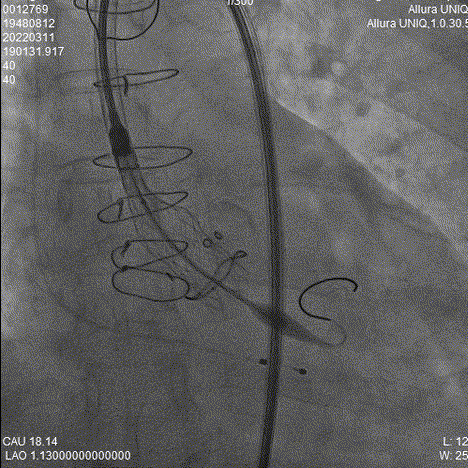

18mm球囊预扩

导丝跨瓣

对侧Snare辅助

Snare辅助过弓

瓣膜释放过程